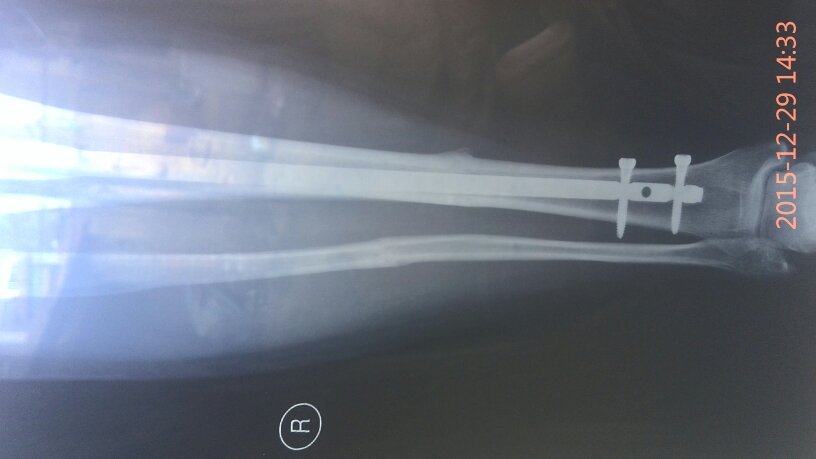

有骨科医生吗?我小腿骨折,上的钢板现在八个月了昨天复查医生说,骨头已经长好,可以取钢板了,我就是问 有骨科医生吗?我小腿骨折,上的钢板现在八个月了昨天复查医生说,骨头已经长好,可以取钢板了,我就是问问八个月了取是不是有点早,心里有点害怕,麻烦帮我看看告诉我,谢谢了…… 点击展开 匿名用户 2015-12-30 19:45 满意回答 怎么骨折的? 匿名用户 2015-12-30 20:55 宝宝知道提示您:回答为网友贡献,仅供参考。 为您推荐: 其他回答 你还是听医生的吧,时间太久了也不太好, 匿名用户 2015-12-30 20:54 没事了,别虚 匿名用户 2015-12-30 20:53 医生的话是对的 华雄40 2015-12-30 19:47 相关问题 小腿骨折钢板固定后,钢板折断且 小腿胫腓骨骨折只放了钢板没有复位这样好吗 我右小腿骨折,手术后有钢板,3个月了外伤口不愈合 是…